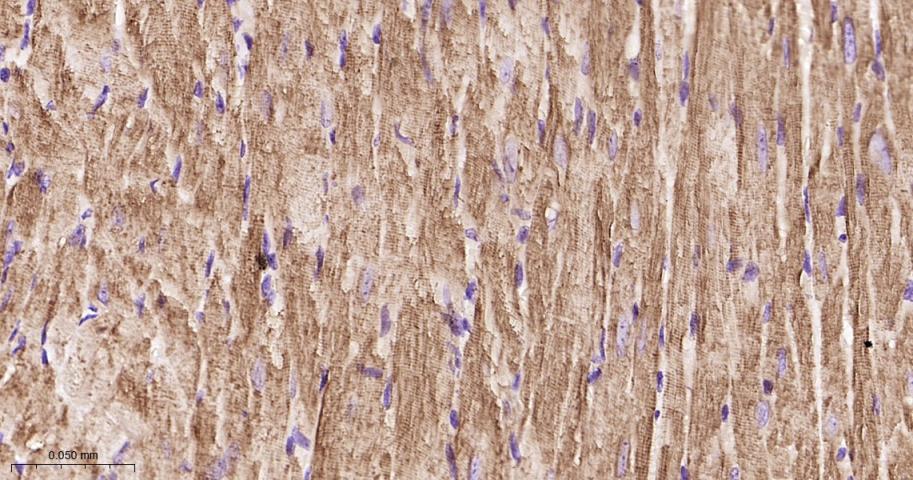

Paraformaldehyde-fixed, paraffin embedded Human Heart; Antigen retrieval by boiling in sodium citrate buffer (pH6.0) for 15 min; The section was incubated with TNNI3 Monoclonal Antibody, Unconjugated (bsm-61955R) at 1:200 overnight at 4°C, followed by conjugation to the bs-0295G-HRP and DAB (C-0010) staining.

Paraformaldehyde-fixed, paraffin embedded Rat Heart; Antigen retrieval by boiling in sodium citrate buffer (pH6.0) for 15 min; The section was incubated with TNNI3 Monoclonal Antibody, Unconjugated (bsm-61955R) at 1:200 overnight at 4°C, followed by conjugation to the bs-0295G-HRP and DAB (C-0010) staining.

Paraformaldehyde-fixed, paraffin embedded Mouse Heart; Antigen retrieval by boiling in sodium citrate buffer (pH6.0) for 15 min; The section was incubated with TNNI3 Monoclonal Antibody, Unconjugated (bsm-61955R) at 1:200 overnight at 4°C, followed by conjugation to the bs-0295G-HRP and DAB (C-0010) staining.